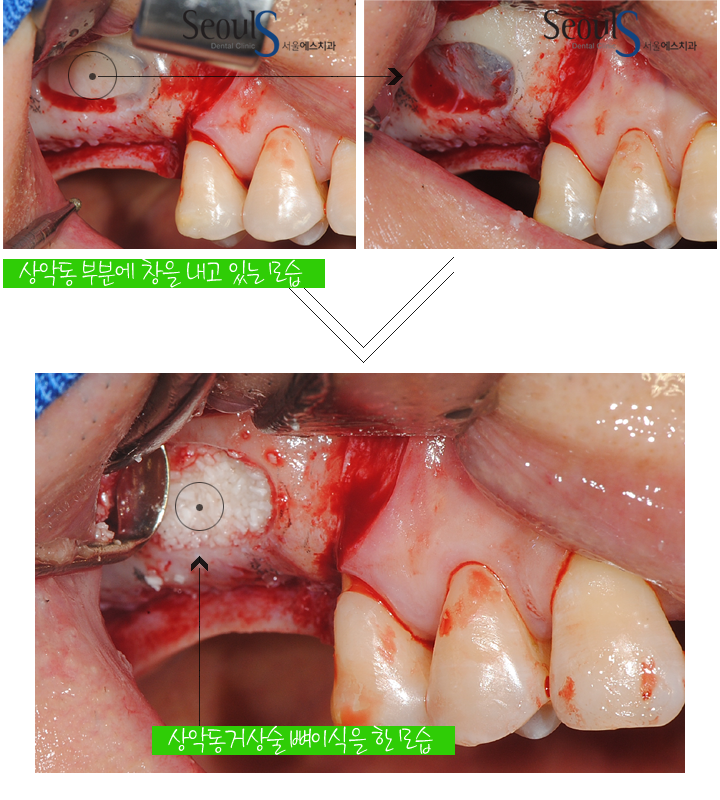

잇몸뼈가 1~2mm 정도 남았을때는 상악동 부분에 창을 내고

그 곳으로 잇몸뼈 이식을 진행하는 상악동거상술을 진행합니다

윗어금니가 빠졌고 잇몸뼈가 거의 없는 상태에서 임플란트 식립을 위해

상악동 부분에 창을 내고 그 곳으로 뼈이식을 진행하고 있습니다